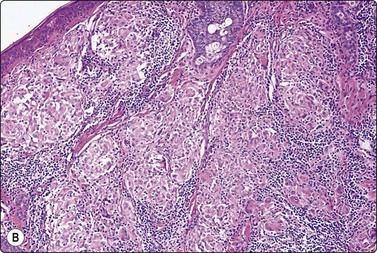

The cytology of nodular hidradenoma30-32 and of clear cell hidradenoma33,34 has been described in single cases. A benign skin adnexal tumor from our files, histologically reported as cystic eccrine hidradenoma, is shown in Figure 14.9. The FNB sample was of mucoid fluid which contained clusters of variably cohesive uniform epithelial cells with a moderate amount of cytoplasm and small dark ovoid nuclei. A dual population was not discernible. The cytology was reported as a benign skin adnexal tumor without further specification.

image image image

Fig. 14.9 Cystic eccrine hidradenoma

Loose clusters of basaloid cells with small, dark, uniform nuclei in a background of proteinaceous fluid (A, MGG; B, Pap, IP); (C) Corresponding tissue section (H&E, LP).